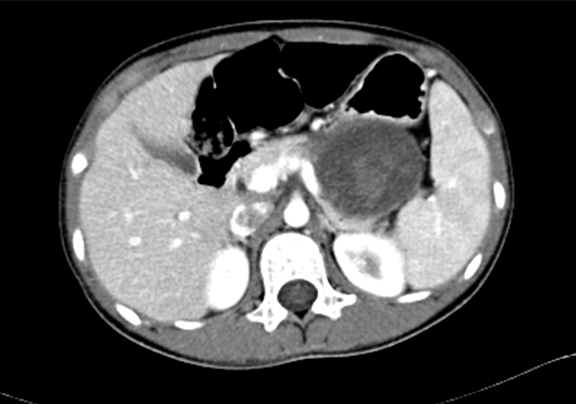

上腹部增强CT+三维:胰腺体尾部囊实性占位病变,考虑偏良性肿瘤可能性大,建议MR 进一步检查

术前CT检查:

动脉期

静脉期

平衡期